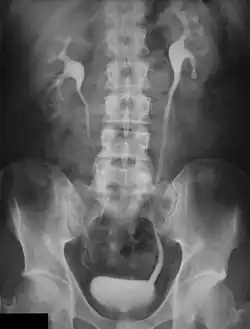

Digital Subtraction Angiography (DSA), as the name implies, involves an image subtraction technique - see Figure 7.1. As will be seen below, the technique involves more than simply applying a subtraction process in the digital image processor. In addition, it will be seen that the type of technology utilised, while based on the design of fluoroscopy systems, needs to incorporate a number of modifications unique to DSA. Before addressing the technology however, some basic physics needs to be introduced which will aid in putting the subsequent technology discussion into context.

- The temporal-averaging feature of digital noise reduction can also be used for image presentation purposes so that the time course of the movement of contrast medium during a study can be displayed using just one image - see an example in Figure 7.4 from the peripheral study shown above - instead of a sequence of numerous images. Such an image is sometimes referred to as a Vascular Trace.

- One method of temporal filtration, referred to as Integrated Mask-Mode DSA involves adding (also called integrating) a number of images, acquired prior to the arrival of the contrast medium, to form an integrated mask image and adding a number of peak-opacification images to form an integrated live image. This is the process that was used to generate the vascular trace image in Figure 7.4. Thus, when four images are used to generate each integrated mask and live images, eight of the 25 images are now used in the subtraction process and, as a result, only 68% of the dose is wasted, and a subtraction image with lower noise results.